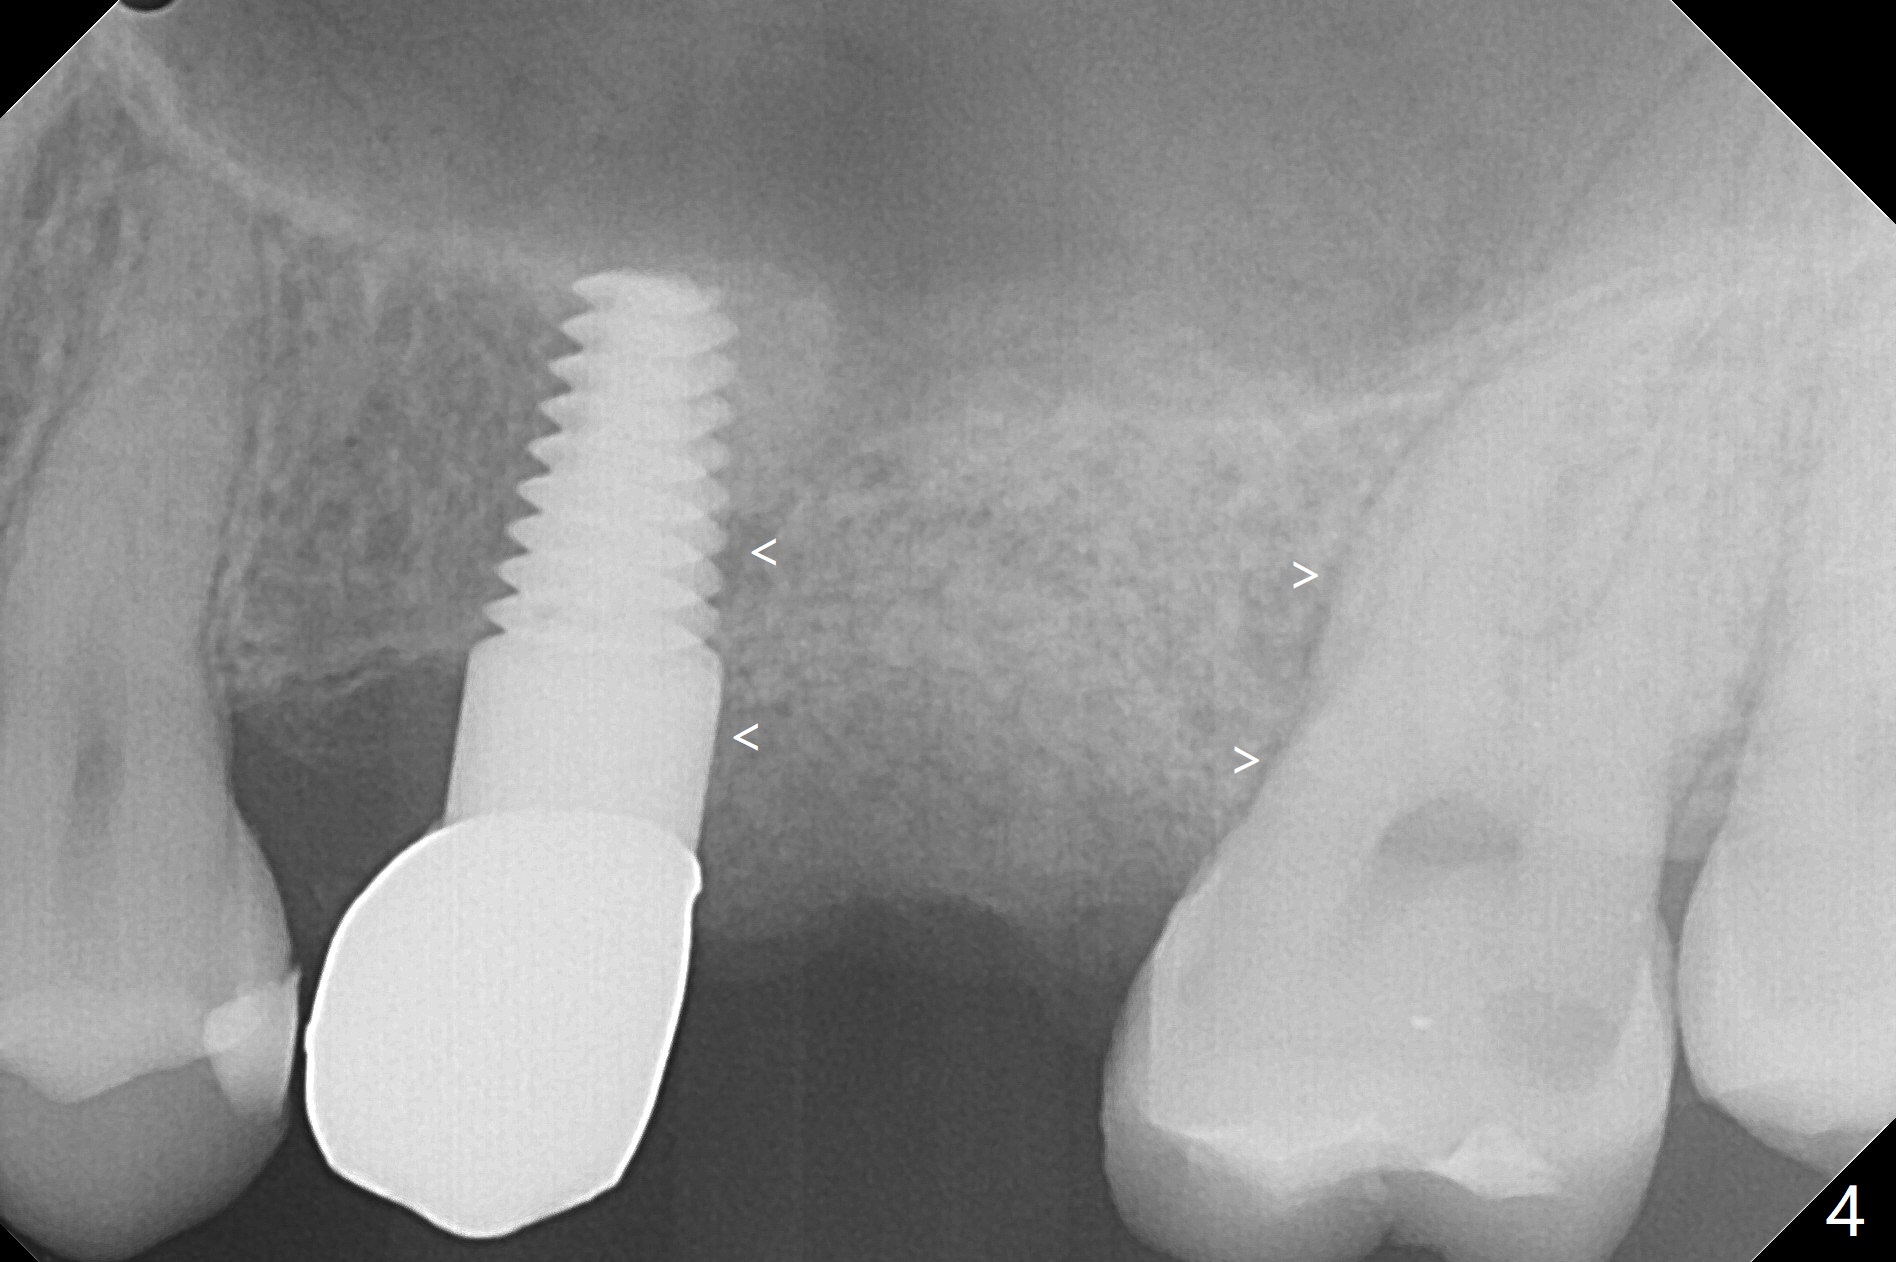

A 32-year-old woman develops periimplantitis (severe hemorrhage and deep pockets) at #14 three years 7 months post cementation (Fig.1).  A 4.5x11 mm implant is placed with flap at #13 after failure for the 1st time (Fig.2), while a 5x11 mm implant is placed flapless with sinus membrane perforation.  Uniposts are cemented with Ketac.  The lingual plate at #14 is defective (Fig.3).  The implant at #14 will be removed flapless, followed by Osteogen plug (most likely sinus floor defect) and bone graft.  After healing, an implant will be placed with guide.  By breaking the proximal contacts, the crown, abutment and implant at #14 are shaken loose using forceps.  Finally the crown breaks off.  Make a slot on the top of the abutment and use a screw bit to turn the abutment/implant counterclockwise.  There is abundant granulation tissue with arterial hemorrhage associated with granulation tissue removal.  The defect involves the distal surface of the implant at #13 and the mesial surface of the tooth #15.  Therefore bone graft is deposited in these surfaces (Fig.4 arrowheads, as compared to preop BW, Fig.4').  The periodontal dressing seems to remain in place asymptomatic 7 days postop (Fig.5).  The bone height 5.5 months postop should be enough for implantation (Fig.6).  To avoid marker associated with guided surgery, free hand will be adopted.  Sinus lift with PRF is expected.  To place in the middle of the ridge buccopalatally, incision will be made with bone expansion.